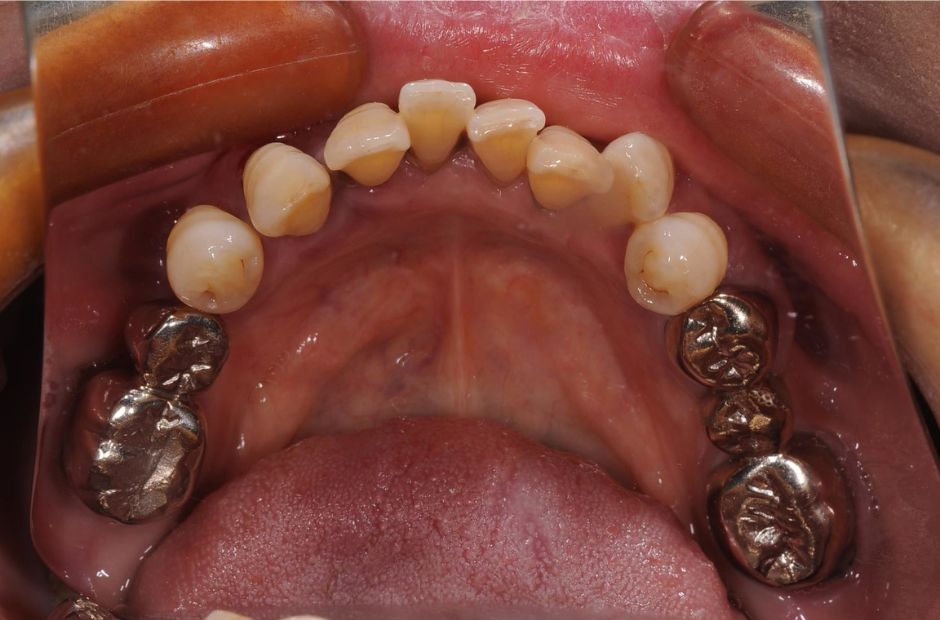

case.01

インプラントで口腔機能の改善

中年の患者様がインプラント治療を希望し来院されました。数本の歯を失っていたため、インプラントを用いて噛む力と審美性を回復しました。治療により、患者様は食事の楽しみを取り戻し、自信を持って笑顔を見せるようになりました。